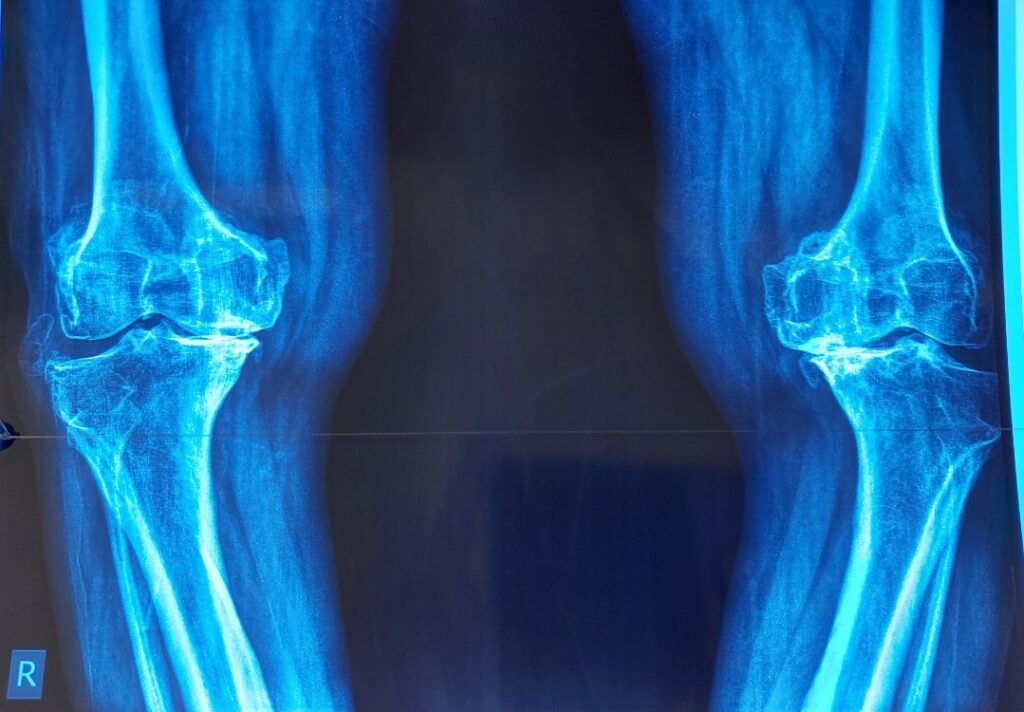

Knee stiffness and pain can severely limit daily activities, especially when joint damage continues to progress despite medications, injections, or physiotherapy. In such cases, total knee replacement can be a long-term and reliable solution. With a growing emphasis on precision and faster recovery, many orthopaedic surgeons are turning to minimally invasive techniques that reduce muscle […]

Recovering from a total knee replacement takes time, effort, and support. If you or someone you care about in Lahore is getting ready for knee replacement surgery, knowing what to expect during recovery can help you feel calm. This guide explains the main parts of recovery after surgery. It also gives tips to help you […]